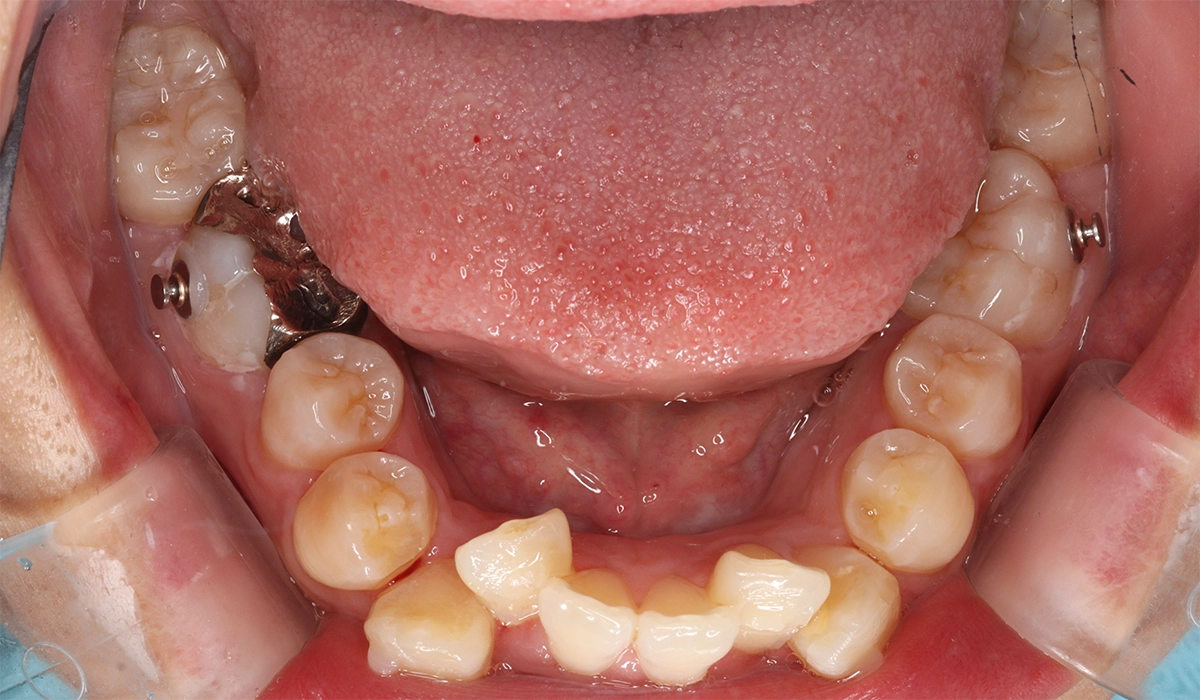

術前:下顎

術後:下顎